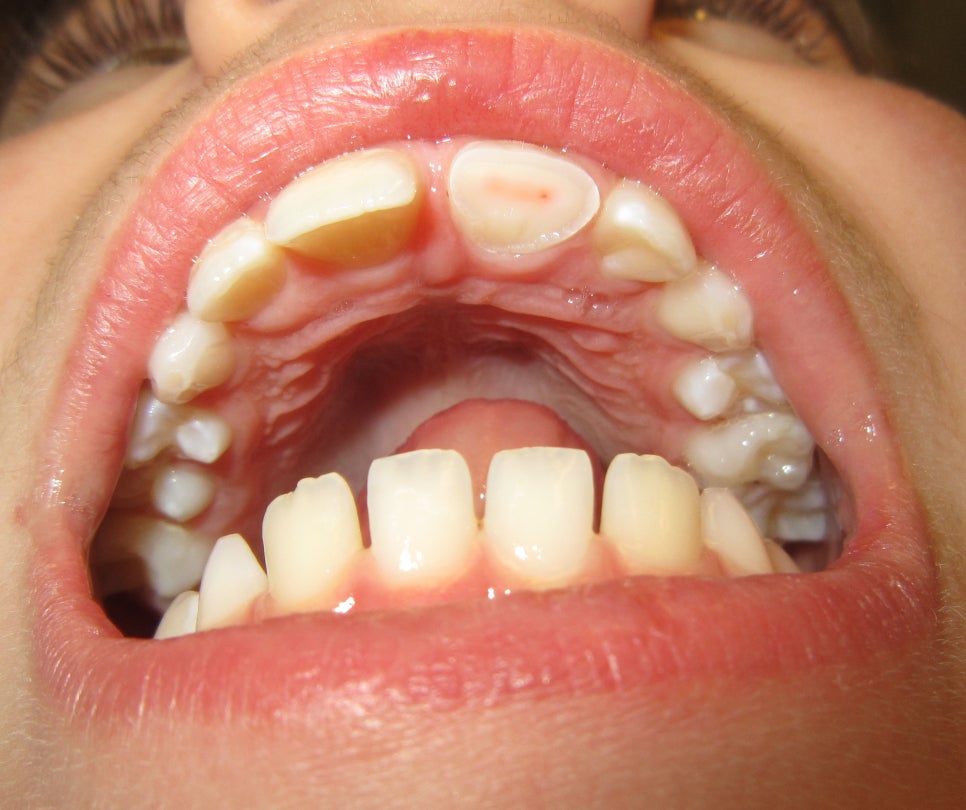

🤔 겉만 깨진 걸까요? 법랑질 파절

법랑질만 깨진 경우(출처: https://en.wikipedia.org/)

가장 가벼운 경우는

치아 겉층인 법랑질(enamel)만 깨진 상태입니다.

통증 거의 없음

시림도 크지 않음

모서리가 날카롭게 느껴짐

이 경우

레진으로 간단히 다듬거나 보강하면

큰 문제 없이 회복되는 경우가 많습니다 🙂

겉면 파절은 비교적 단순하지만, 방치하면 균열이 커질 수 있습니다.